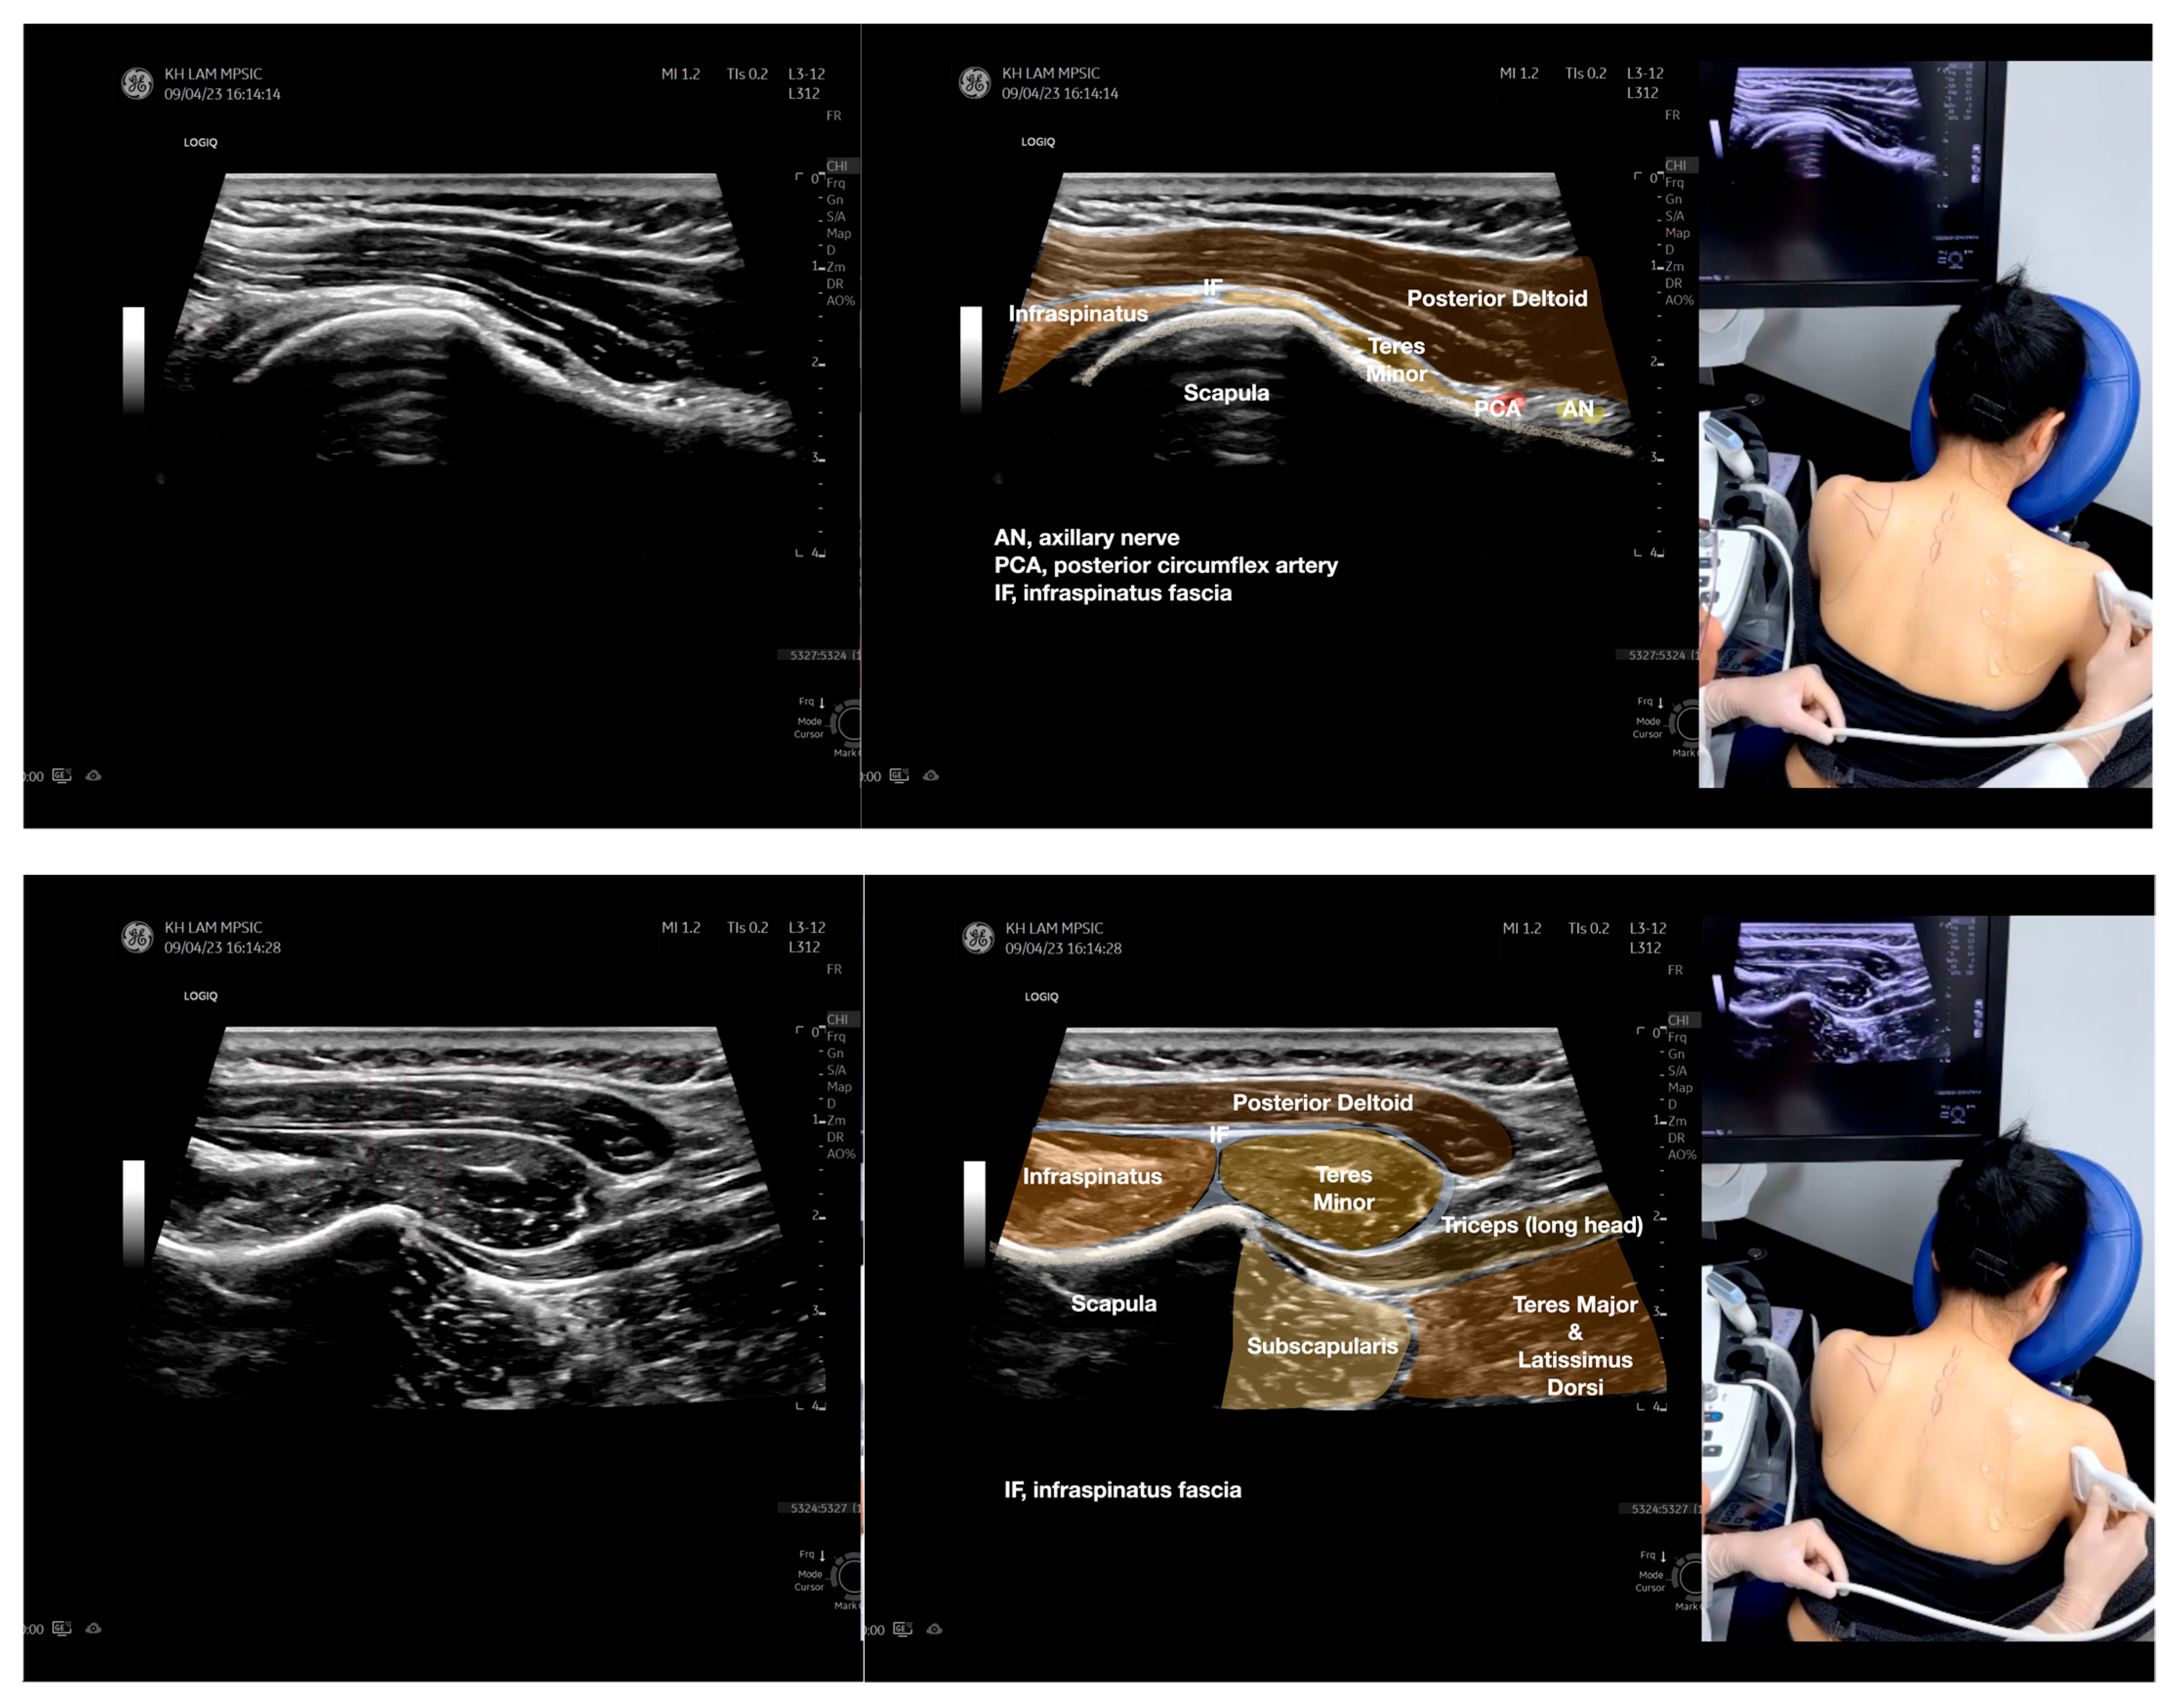

Figure 3.

Sonoanatomy of the lateral boarder of the scapular, its related muscles, and the infraspinatus fascia. Video S7 has demonstrated the step-by-step scanning techniques of these structures shown in this figure. Available online: https://www.dropbox.com/s/891m19vvw6bak34/Figure%203.docx?dl=0 (accessed on 1 January 2023).